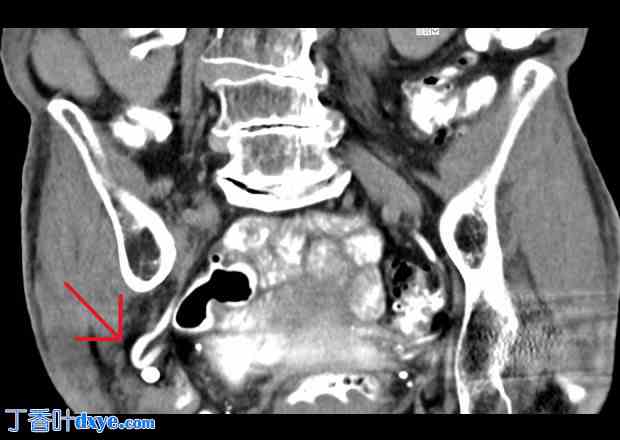

一位79岁、体型偏瘦的德国女性因右侧腰痛就诊,疼痛已持续数周,前一天晚上加剧。她自述疼痛与活动和体位相关,此前曾被诊断为腰椎综合征。她否认有排尿困难、尿急、血尿、尿频、大便不规律、发热或寒战等症状。既往病史包括II型糖尿病、肝肾囊肿、慢性阻塞性肺疾病(COPD)和无症状性胆囊结石,但无腹部手术史。体格检查发现右下腹和中腹疼痛,无腹膜刺激征,未触及疝或腹壁膨出。此外,肾区未见隆起或压痛。实验室检查显示轻度白细胞增多(12.8 Gpt/L)和C反应蛋白(CRP,18 mg/L),但血常规、电解质、肾功能指标、转氨酶和尿液检查结果均正常。腹部超声显示右肾I级尿潴留。计算机断层扫描(CT)初步提示右侧膀胱憩室位于闭孔疝区域。然而,后续的泌尿系统影像学检查显示输尿管远端疝入右侧闭孔管,输尿管扭曲导致I级肾积水(图1)。患者入院接受止痛治疗。由于随访实验室检查显示肾功能正常,肠道功能也未受损,因此无需立即干预。疼痛缓解后,患者于3天后出院。

图1

CT扫描显示右侧输尿管疝入右侧闭孔管,并导致输尿管扭曲(红色箭头)。